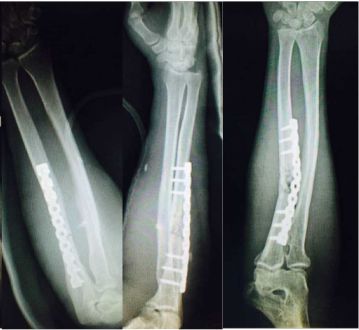

两处腓骨钢板多余(因为下胫腓骨联合没有损伤,特别注意不要犯这种错误)(髓内钉加阻挡钉首选,其次内侧长钢板,如果没有钢板用外固定架也可以)

胫骨远端简单骨折选用钢板固定没有实现坚强固定,钢板承受应力,孔处应力集中断裂

更换长钢板后愈合

应力集中断裂。内固定过于坚强,钉子粗,钢板与过度处应力集中(没有必要手术,必须手术可以用随内针加石膏固定)。

补救:取下一枚钉子骨折愈合了,关键是取钉子后减少了应力集中,延长了钢板的寿命,骨折愈合了。如果骨不愈合钢板迟早断裂(钢板当初放在内侧会好,蝶形骨块不会坏死,腓骨固定后外侧稳定,内外柱均衡愈合机会增加,当然最好还是髓内钉)。

取下3枚钉子骨折愈合了,与上一例同一位医生所做。张力带钢板,去除3螺钉后,钢板的应力分散,弹性增加,骨折端承受有效的应力刺激,最后骨折愈合。去除螺钉的时候如果加骨皮质剥离重新激发骨愈合会更好。(最好选髓内钉)